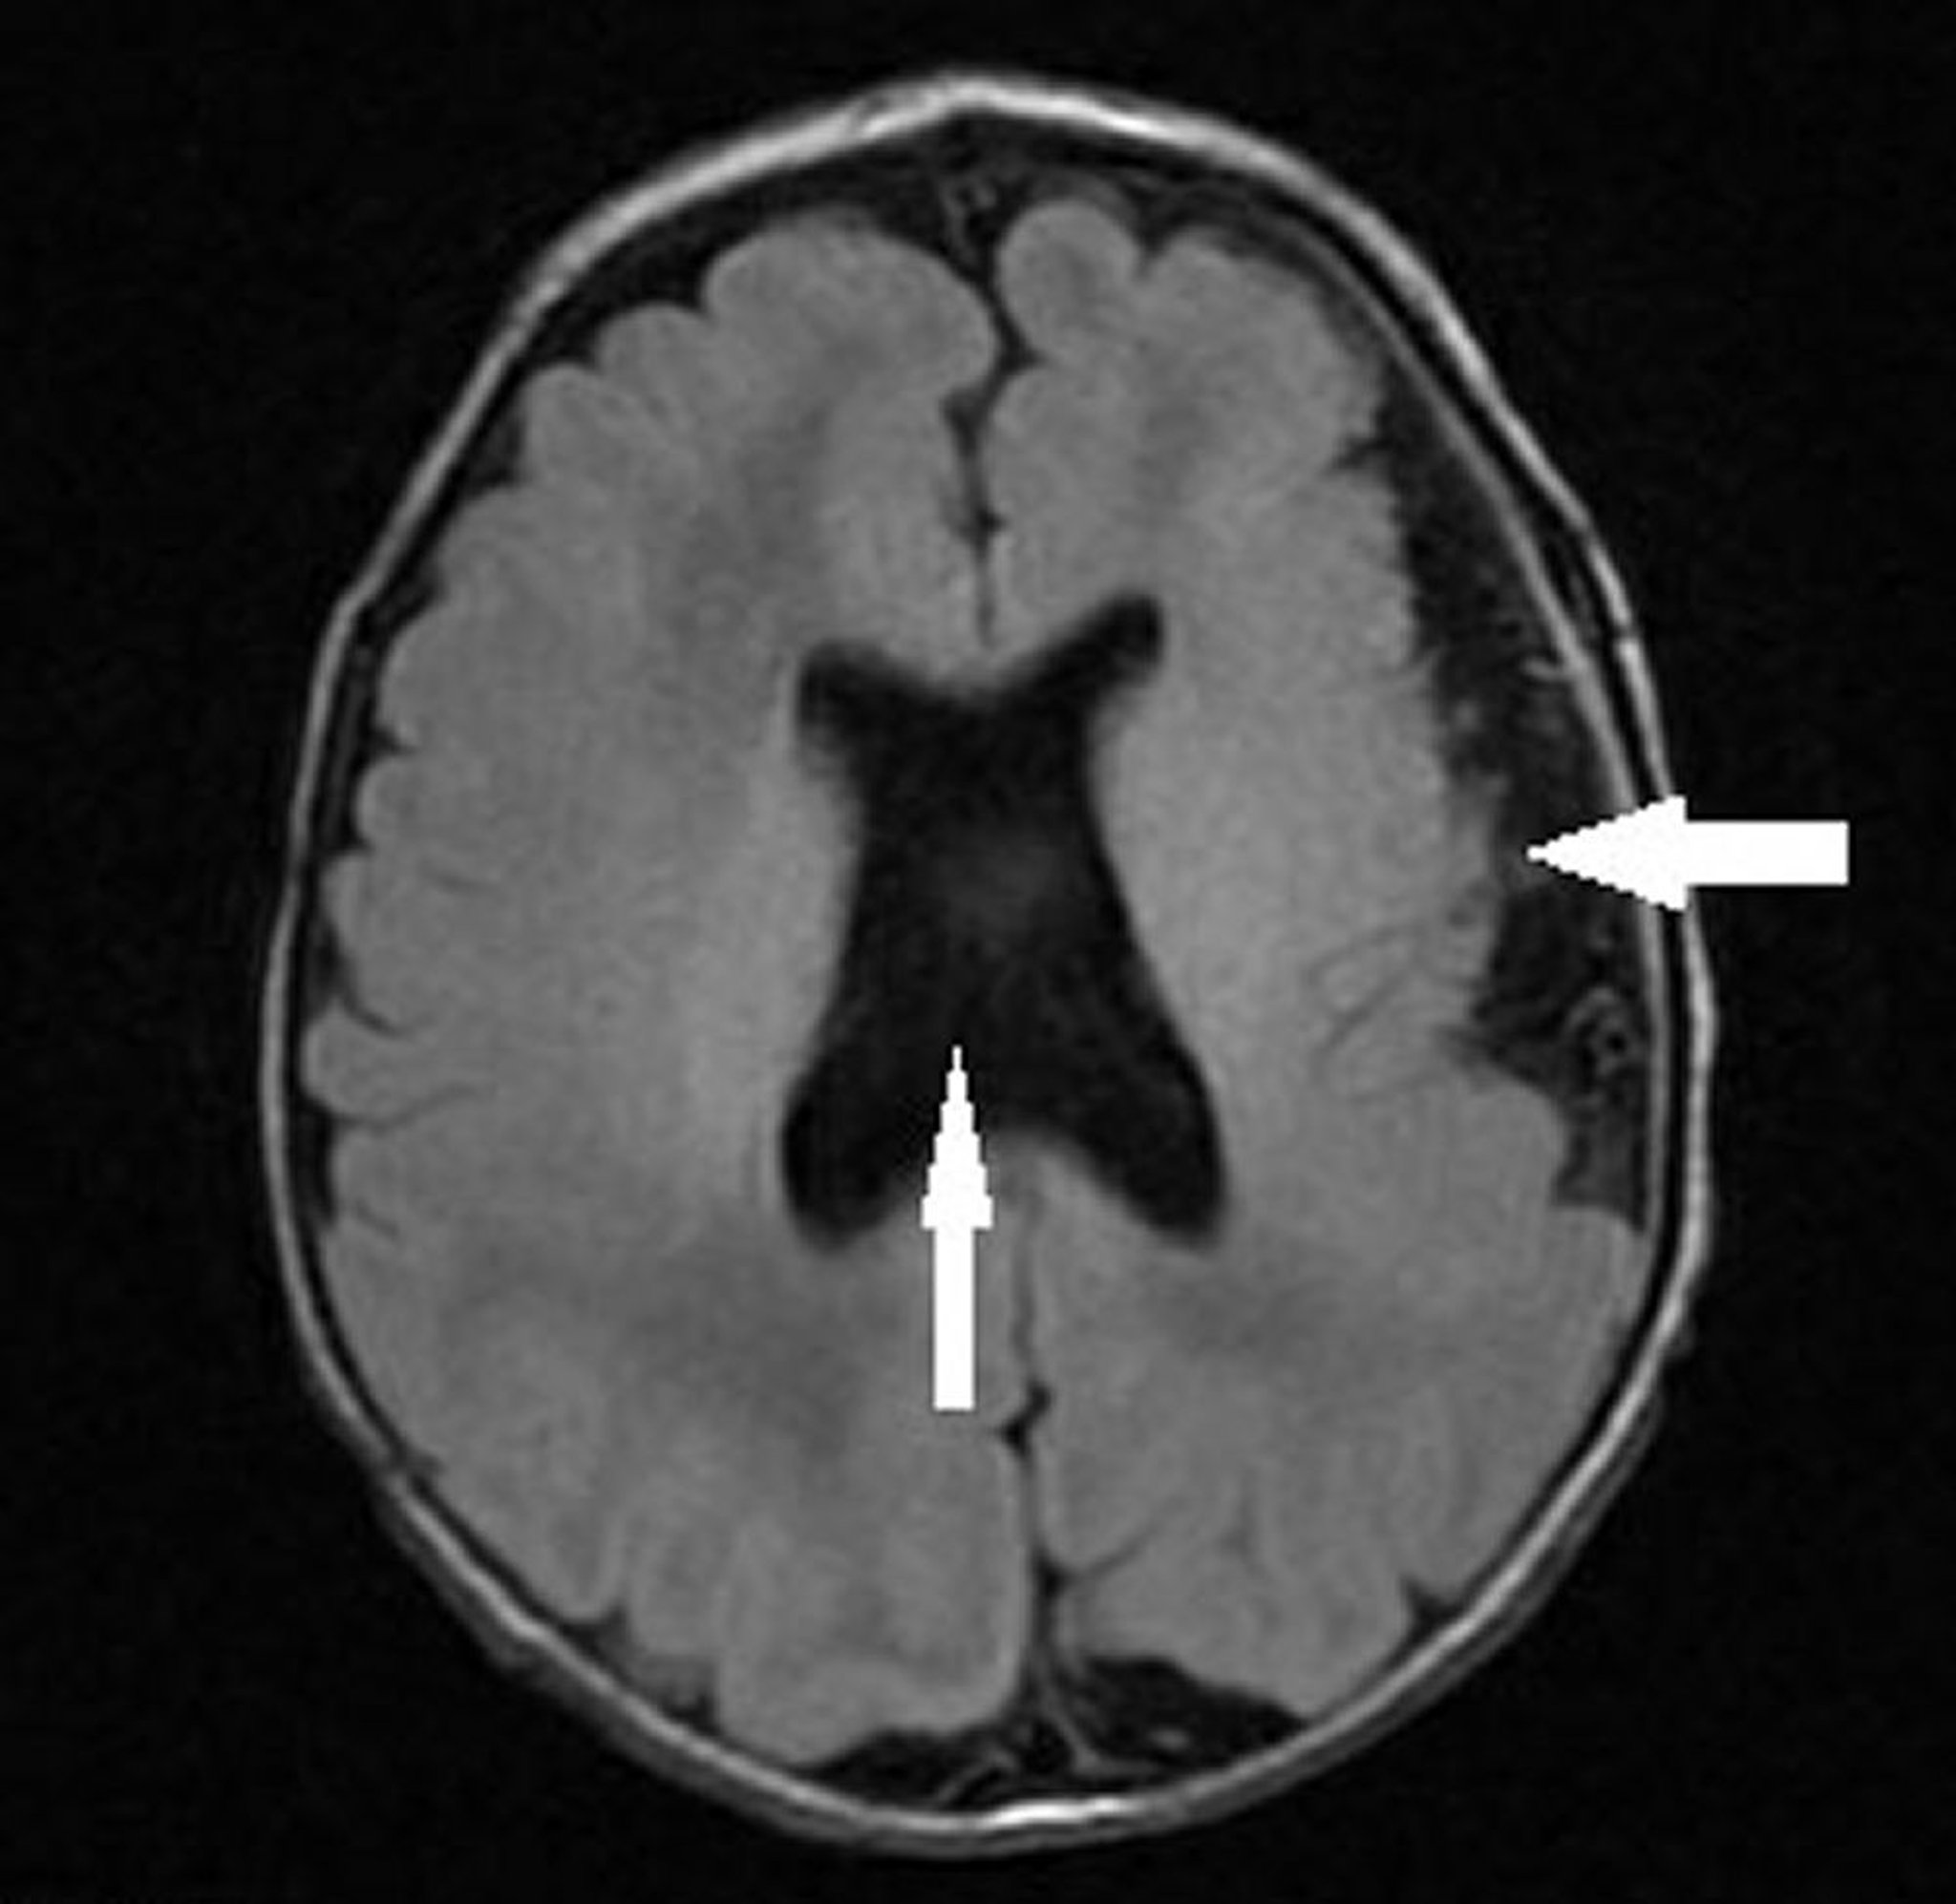

中隔視神経形成異常症を伴う多小脳回症

この乳児の画像には,左大脳半球の多小脳回症(左向き矢印)に加えて,中隔視神経形成異常症と一致する脳室形状の異常(視神経低形成,透明中隔の欠損または異常,および下垂体低形成)を伴う透明中隔の欠如(垂直方向の矢印)が認められる。